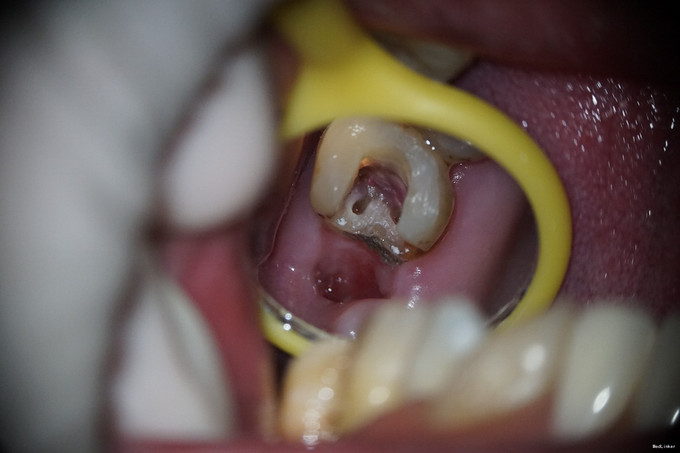

诊断:27牙慢性牙髓炎 治疗方案: 1、27牙根管治疗+充填修复+冠修复 2、27牙显微根尖外科手术 3、27牙干髓术 4、46牙择期治疗 经与患者详细介绍每种治疗方案的治疗经过、费用及预后,患者选择方案1。 治疗经过: 初诊:因患者咽反射强,无法上橡皮障。27牙涡轮机去龋,未去净龋坏时见穿髓孔,但因髓腔钙化及解剖牙冠长,不能探及明显髓腔结构;ET20清理髓腔内钙化,探及3根管口。其中近颊根根管口探痛明显,封“三聚甲醛”;CAVITON暂封。 首次复诊:27牙去净暂封,根测仪测定根管长度,近颊根19mm,远颊根19mm,腭根20mm;机用镍钛器械Protaper清扩至#2506锥度,腭根清扩至#3504锥度,示尖到位;超声荡洗,次氯酸钠冲洗,纸尖吸干,根管内封氢氧化钙,髓腔置干棉球,CAVITON暂封。 二次复诊:27牙去暂封,去棉球,超声荡洗根管,次氯酸钠冲洗,再次测量根管长度,纸尖吸干,AH糊剂+大锥度牙胶尖封闭根尖段,热牙胶封闭根中上段,拍片示根充到位;腭根预备纤维桩道,冲洗,干燥,粘接#13纤维桩;涂布粘接剂,流体树脂垫底,3M纳米树脂充填修复,调he,抛光。

1、从全景片中可见,该牙龋坏已与髓腔相通,髓腔较为明显。但开髓时发现,髓腔内几乎均钙化,髓腔空间及其狭小。且该牙解剖牙冠长,且为上颌最后颗磨牙,若对牙体解剖没有足够地掌握,没有充足的经验,非常容易开髓开偏或找不到根管口,或有遗漏根管,因为近颊根根管口被钙化的牙体组织完全覆盖。此种情况下,若使用涡轮机企图去除牙体组织后寻找根管口非常困难,若在显微镜下使用超声则为最佳选择。 2、该牙虽然冠的上部牙体组织无去坏,但仍然去除掉了。虽然对牙齿的创伤较大,但若不去除这些无机釉,一来可能龋坏无法去除干净,二来抗力形不足,容易折断。 3、该牙髓腔内牙髓完全坏死,但各个根管内均有较好牙髓活力。说明牙髓的坏死是一个渐进的过程,即便是髓腔及根管开始钙化,牙髓也可有活力。